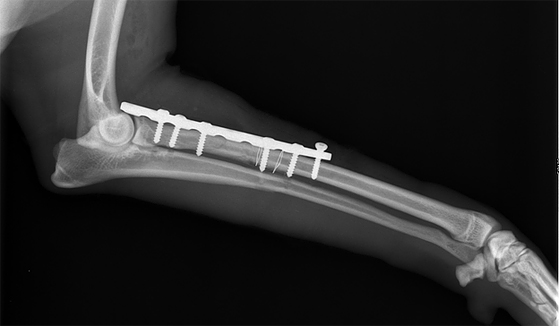

Перелом локтевой и лучевой кости у собаки

Контрольный рентгеновский снимок того же животного после проведения остеосинтеза